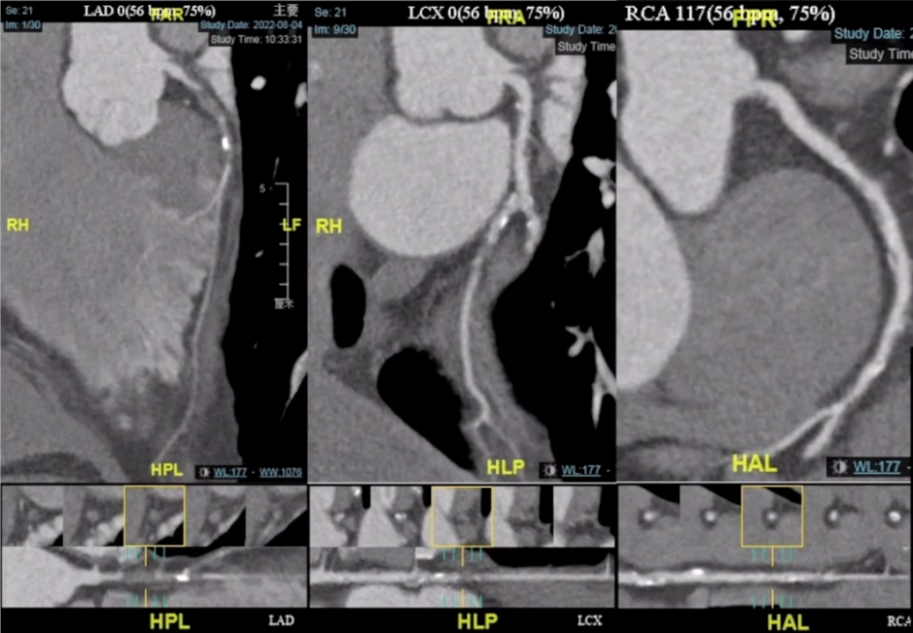

入院后冠脉CT检查如下所示:前降支(LAD)近段闭塞病变,闭塞段长度>2cm,闭塞段体部有少许钙化灶。